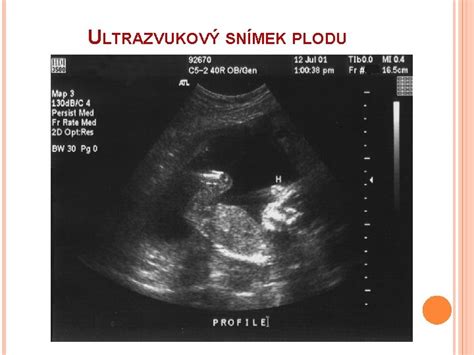

Čo sa zisťuje na 2. ultrazvukovom screeningu: V druhom trimestri, zvyčajne medzi 18. až 22. týždňom, sa vykonáva druhý ultrazvukový screening. Tento podrobný ultrazvuk sleduje rast a vývoj dieťaťa, kontroluje anatómické štruktúry a odhaľuje prípadné anomálie. Okolo 24. až 28. týždňa sa tiež vykonáva test na tehotenskú cukrovku (oGTT).